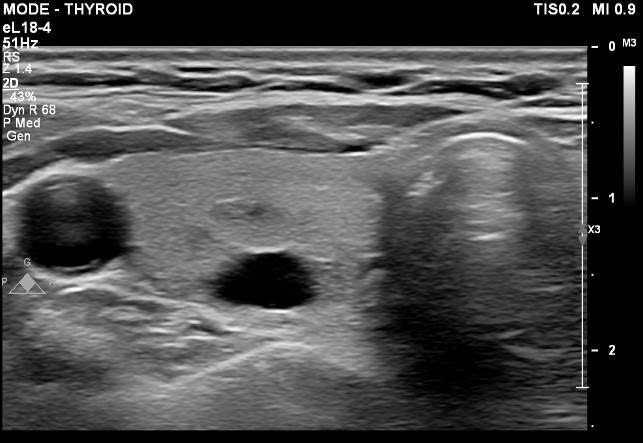

Ảnh siêu âm nang tuyến giáp - Ảnh BVCC

Siêu âm tuyến giáp là phương pháp đơn giản, an toàn và để đánh giá nang tuyến giáp. Hình ảnh siêu âm cho phép bác sĩ xác định kích thước, vị trí và đặc điểm của nang, từ đó phân loại mức độ cần theo dõi. Khi cần thiết, bác sĩ có thể chỉ định chọc hút dịch nang vừa để giải áp, vừa để xét nghiệm tế bào nhằm đánh giá bản chất tổn thương.